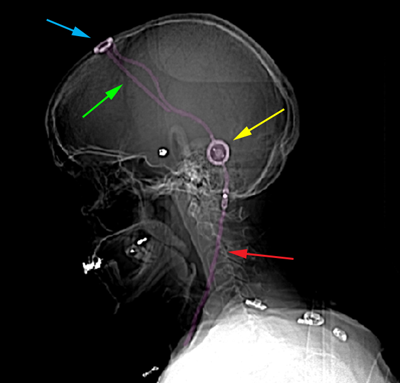

Περιγραφή Το σύστημα κοιλιοπεριτοναικής παράκαμψης περιλαμβάνει 3 βασικά μέρη: τον κοιλιακό καθετήρα, τη βαλβίδα, και τον περιτοναϊκό καθετήρα. Ο κοιλιακός καθετήρας τοποθετείται στο μετωπιαίο ή ινιακό κέρας της, δεξιάς συνήθως, πλαγίας κοιλίας με κρανιοανάτρηση, διάνοιξη δηλαδή μικρής οπής στο οστό του κρανίου, μετωπιαία ή ινιακά αντίστοιχα. Από την οπή της κρανιοανάτρησης εισέρχεται λεπτός καθετήρας από σιλικόνη, ο οποίος φτάνει διαμέσου του εγκεφαλικού παρεγχύματος στην πλάγια κοιλία του εγκεφάλου προκειμένου να παροχετευθεί το Ε.Ν.Υ. Ο καθετήρας συνδέεται κατόπιν κάτω από το δέρμα με μια βαλβίδα, ρυθμιζόμενη ή μη, η οποία εμφυτεύεται επίσης κάτω από το δέρμα περίπου 2 εκατοστά πίσω από το δεξιό αυτί. Η βαλβίδα συνδέεται με τη σειρά της στον περιτοναϊκό καθετήρα σιλικόνης ο οποίος διατρέχει, πάντα εμφυτευμένος κάτω από το δέρμα, από την βαλβίδα-διαμέσου της περιοχής του τραχήλου και τους θώρακα δεξιά-έως την κοιλιακή χώρα. Η είσοδος του καθετήρα στην περιτοναϊκή κοιλότητα απαιτεί διάνοιξη μικρής τομής στο κοιλιακό τοίχωμα, μήκους λίγων εκατοστών. Στην τελική του μορφή το σύστημα παροχετεύει Ε.Ν.Υ. από το κοιλιακό σύστημα του εγκεφάλου στο περιτόναιο με ενδιάμεσο την βαλβίδα της οποίας η πίεση διάνοιξης, όταν είναι ρυθμιζόμενη, μπορεί να μεταβάλλεται με ειδικό εξωτερικό ρυθμιστή (πάνω από το δέρμα) ανάλογα με τις ανάγκες του ασθενούς (περισσότερη ή λιγότερη παροχέτευση Ε.Ν.Υ.). |

Σύστημα κοιλιοπεριτοναϊκής παροχέτευσης με βαλβίδα. Κοιλιακός καθετήρας (εισέρχεται στο κοιλιακό σύστημα του εγκεφάλου) με πράσινο βέλος, ρεζερβουάρ Ε.Ν.Υ. με κυανό βέλος, βαλβίδα ρύθμισης της πίεσης με κίτρινο βέλος, περιτοναϊκός καθετήρας με κόκκινο βέλος. |